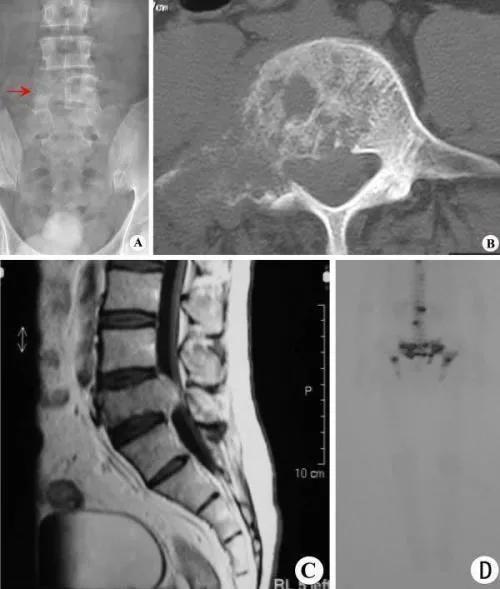

7,老年癌易发生骨转移,男性高于女性。肺癌多转到肋骨,前裂腺癌多转于腰椎和骨盆骨,女性乳腺癌也多转移到肋骨、腰椎、骨盆骨。